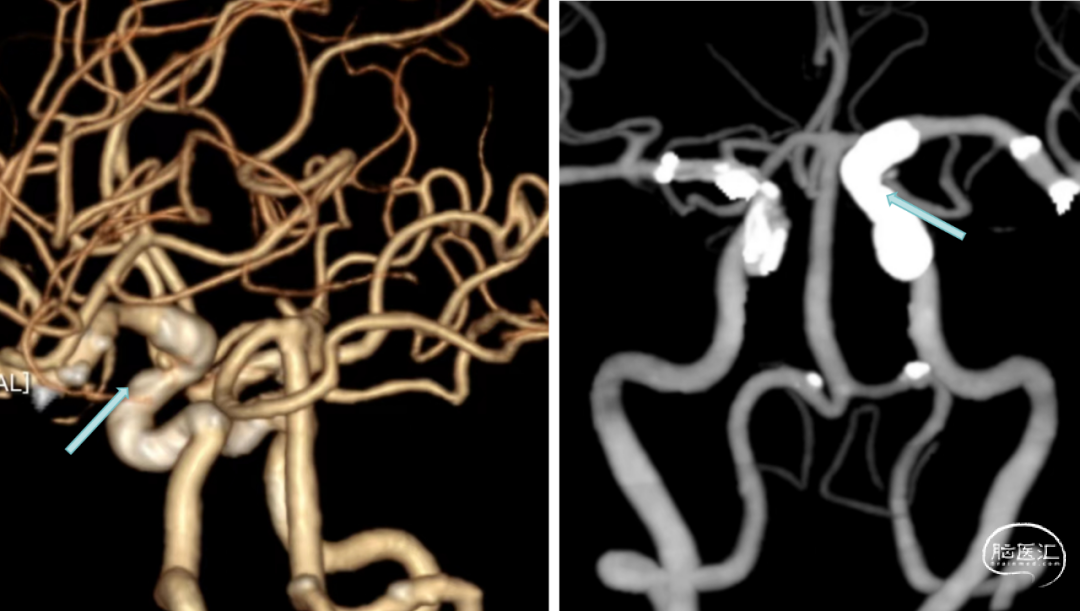

沿支架微导管输送Nuva®血流导向密网支架,待支架头端显影点与微导管齐平,支架输送到位,整体回撤微导管和支架至合适的锚定位置,在大脑中M1中段原位释放密网支架。

支架顺利打开,造形可见支架贴壁良好。

术后4个月复查造影示动脉瘤未愈合。

术后8个月复查CTA示夹层动脉瘤愈合。

1.该病例为多发脑动脉瘤、左侧颈内动脉末端夹层动脉瘤,动脉瘤近远端直径差较大血管迂曲,动脉瘤远端有脉络膜前动脉,传统支架金属填塞弹簧圈有闭塞脉络膜前动脉可能,且复发率较高。很难达到理想的栓塞效果。Nuva®血流导向密网支架操作简便,可以进行原位释放,30%-35%的金属覆盖率起到显著的血流导向作,有利于管腔重建,提高治愈率。